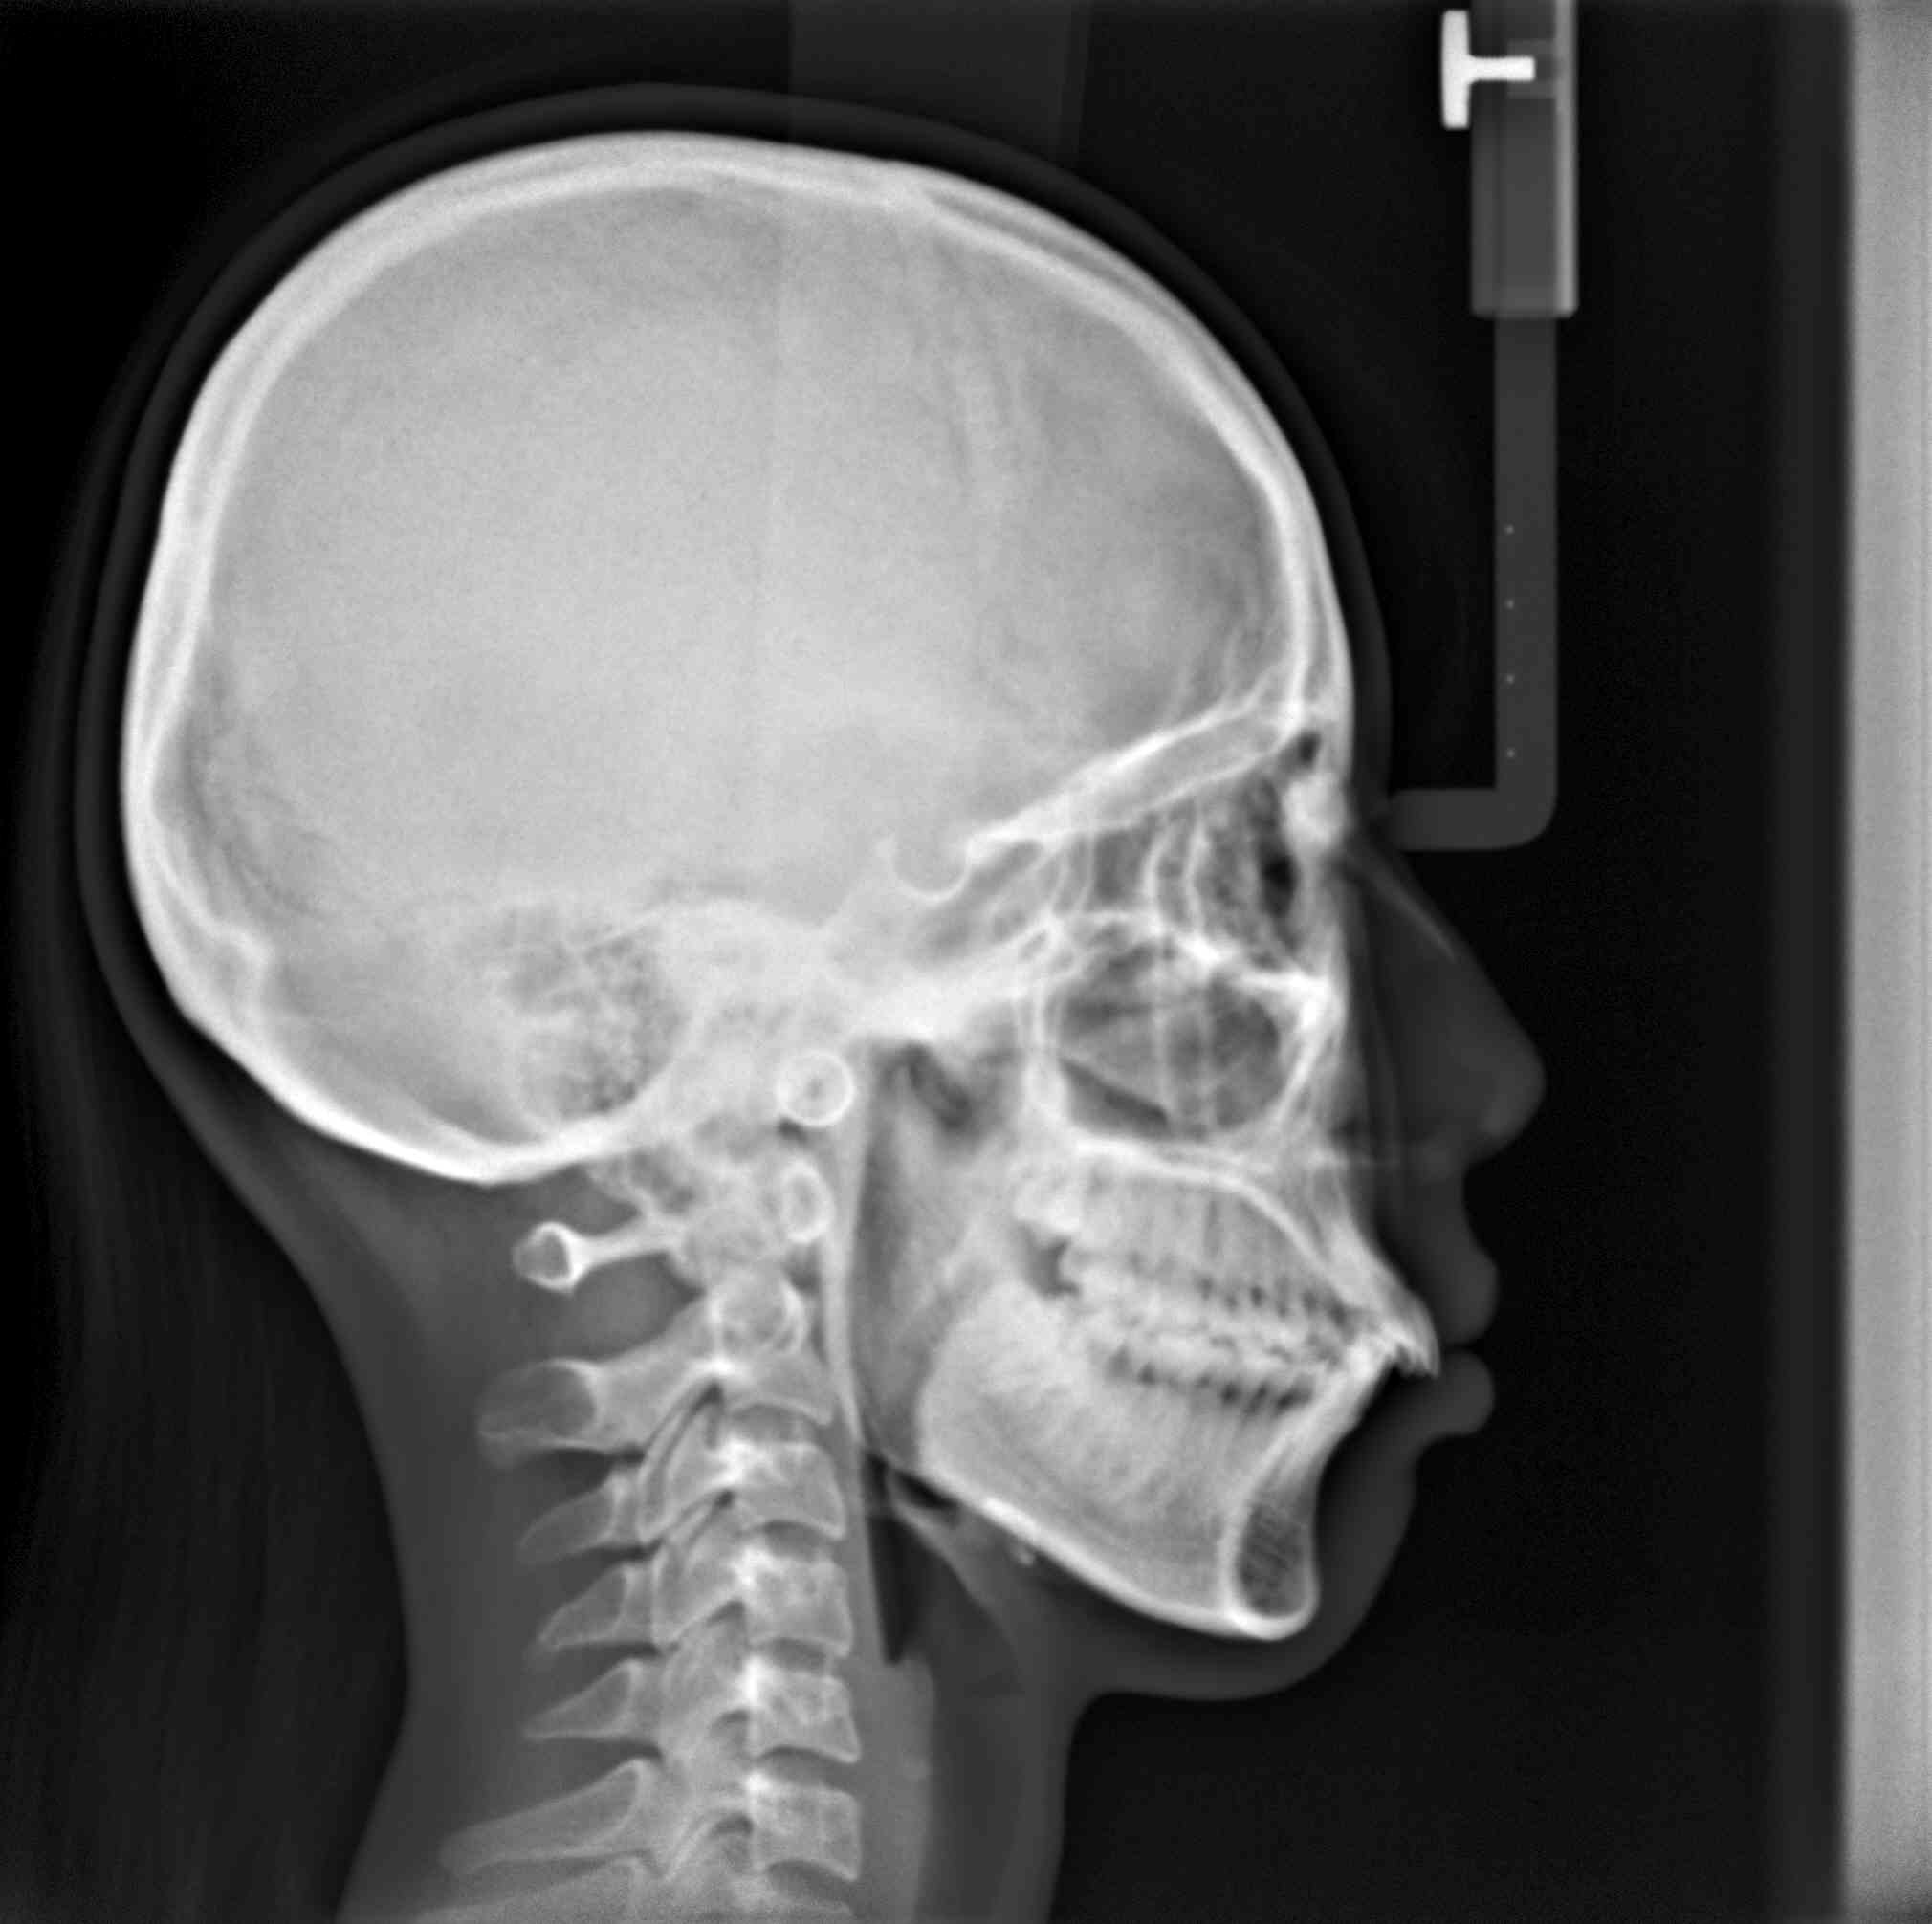

隱適美拔牙改臉型(二) 首頁 案例分享 齒顎矯正 隱適美拔牙改臉型(二) 拔牙改臉型案例 年紀:20 歲 女性 治療方式:隱適美隱形矯正 時間:29個月 主訴:外觀看起來比較暴,希望可以把牙齒排列整齊以及後縮 矯正前 矯正後 矯正前 矯正後 矯正前 矯正後 聲明:本所療程皆由專業醫生評估後,依照個人口腔狀況進行治療。因每位患者個別狀況不同,術後狀況也不盡相同,需親來本所由醫生評估。